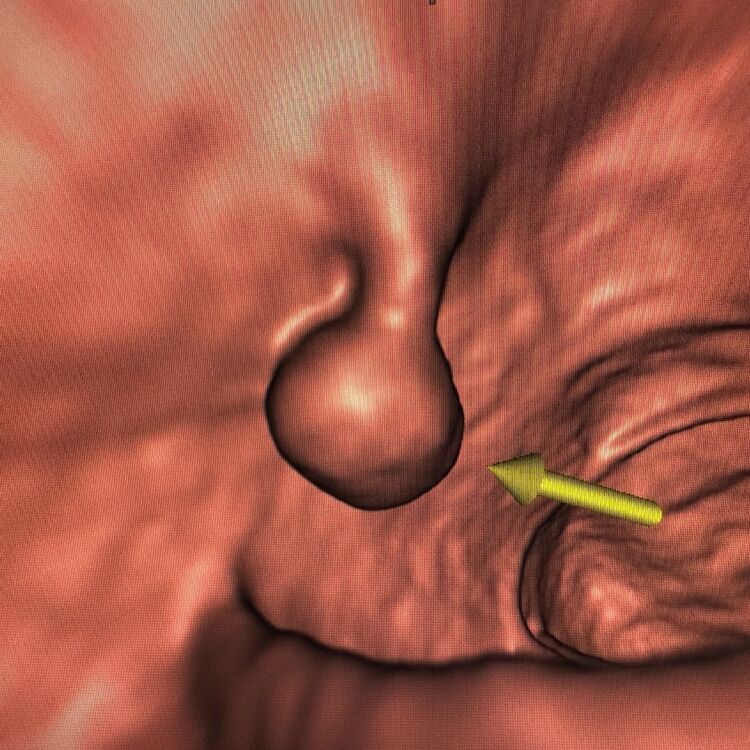

14mm diameter stalked polyp in patient with no symptoms and FIT test negative. CT colonography has identified the polyp using an endoluminal display

CT Colonography